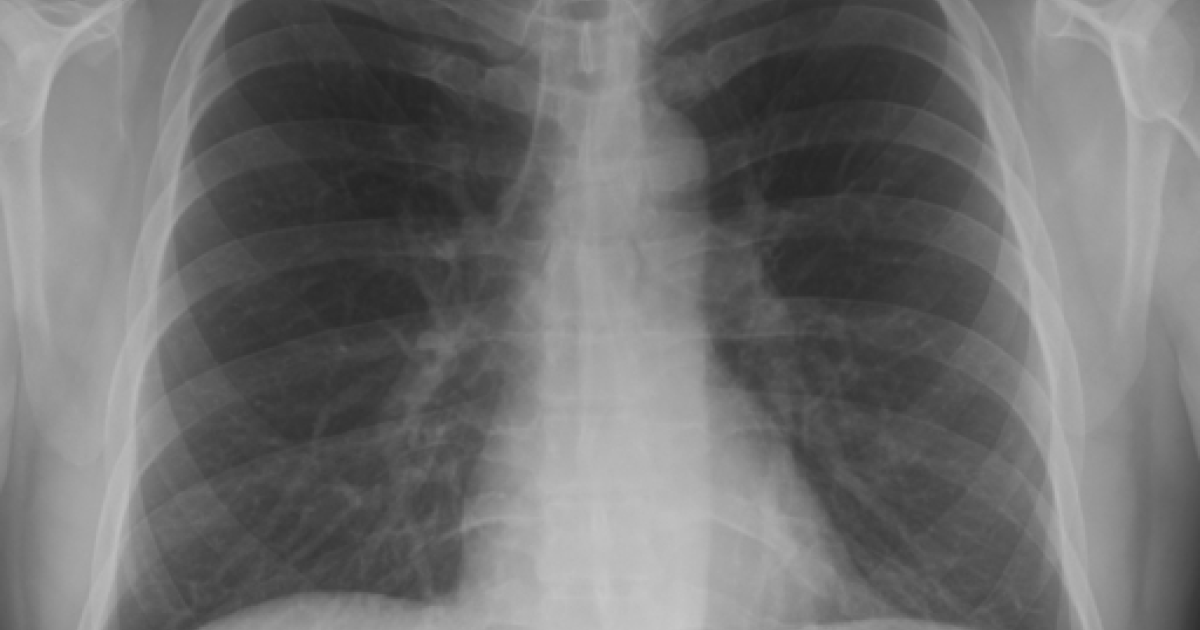

While the natural question is how to reduce the backlog, the underlying, more important question is: "What test allows physicians to be content waiting 30 days for a clinical result?" That problem does not require an algorithm; it requires a discussion, presumably within the NHS, regarding the purpose of these tests. There are limited reasons to order a chest X-ray: as part of a protocol, or to diagnose or follow up on a clinical problem.

In the U.S. a pre-operative chest X-ray is a typical protocol-driven test. As Choosing Wisely, the program to reduce unnecessary testing points out, while many hospitals require them and that number is decreasing, as pre-operative chest X-rays are largely unnecessary outside limited conditions. The necessity for a rapid answer to a diagnostic X-ray should be self-evident. Perhaps a 30 window is acceptable if you're following up on a diagnostic problem? More often than not those problems involve cancer or infection, and chest X-rays are just not the best imaging option.

Examination requires time. Looking at a patient’s chest as they breathe, tapping the various areas of the chest to listen for hollow versus dull sounds, and then listening to the lungs front and back takes a minute, even two. And that doesn’t include the additional minutes required to enter the findings into the electronic record. Before you know it, a third of that 15-minute visit is lost – and that doesn’t even allow for time to explain what you might have found, as well as the doctor's treatment plan. By contrast, it takes 15 seconds to order the chest X-ray.